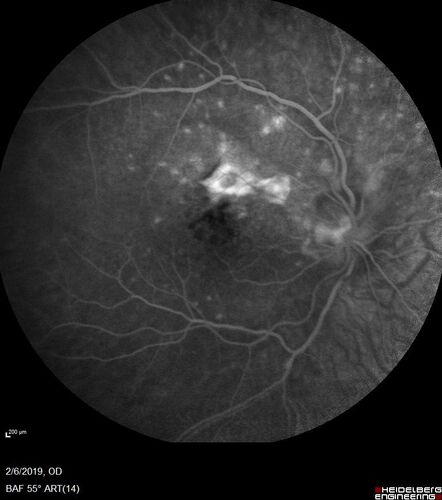

PIC which evolved into Subretinal Fibrosis

27 year old female VA 20/200 right eye 20/20 left eye. Right was treated with lucentis. When extended to 3 months, the fibrosis got much worse

PIC with subretinal fibrosis